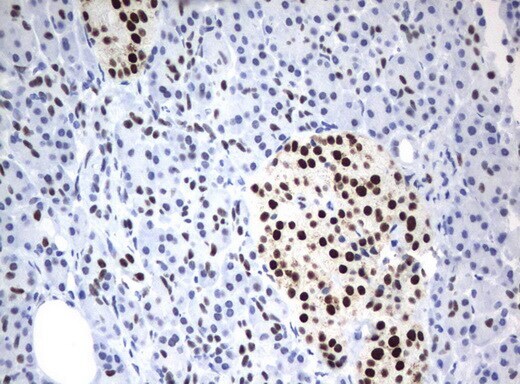

- Immunohistochemical staining of paraffin-embedded Carcinoma of Human pancreas tissue using anti-ZSCAN18 mouse monoclonal antibody. (UM500081; heat-induced epitope retrieval by 10mM citric buffer, pH6.0, 120°C for 3min)